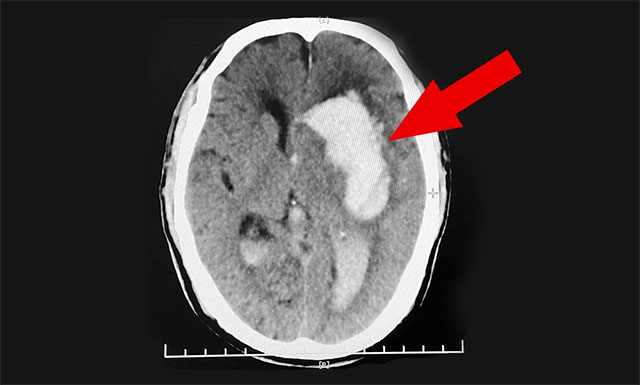

送到医院后,紧急行头部CT检查,根据影像提示及其他相关检查,患者程先生左侧基底节区脑出血,并破入脑室,且出血量很大,临近功能区;伴左侧高颅压,其双侧大脑半球深部多发腔梗,情况非常危急。医生把情况告知郭女士,若手术治疗风险很大,即使保住了生命,也很可能长期偏瘫在床,让她及家属做好心理准备。郭女士听后感到“天塌了一般”,简直无法接受。

“患者紧急转入我院,当时其格拉斯哥昏迷 (GCS) 评分仅有7分 (GCS总分为15分,分数越低其意识障碍越重),处于昏迷状态,意识障碍比较严重,不能言语,右侧肢体活动障碍严重;且患者岁数较大,出血范围较广,出血量大约为50ml,情况危急不容乐观……”,潘仁龙主任这样回顾道,对患者程先生刚入院时的危重病情至今历历在目。

▲ 患者突发脑出血昏迷不醒,病情危急需及时手术

鉴于患者病情危重,潘仁龙主任紧急组织专家团队会诊,根据患者目前的病情、病症及影像检查结果,潘主任与吴博士一致认为患者程先生脑出血严重,已破入脑室,出血量又大,且左侧高颅压,其血压收缩压当时更是高达208mmHg,如果不及时手术治疗,还会有再次出血的风险,因此患者需及早手术清除颅内血肿和降颅压,否则随时会有生命危险。